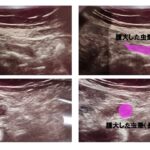

上行結腸に、3/4周性腫瘍(ボールマン2型)が見つかりました。

上行結腸の奥にある盲腸まで行くために、腫瘍内腔を通過するとわずかに管腔が広がったように観察されます。

③硬便が滞留すると、腸管内圧があり、腫瘍内腔が僅かに開き(2番目にのせた内視鏡画像参照)、硬便とともに滞留していた水様便が排泄される。